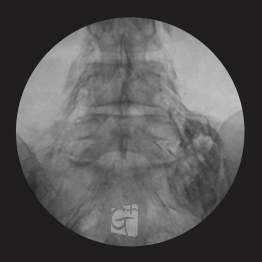

요추 선택적 신경치료

요추 5번에서 시행된 선택적 신경치료 약물이 신경근과 추가공 안쪽으로 잘 퍼지는 모습